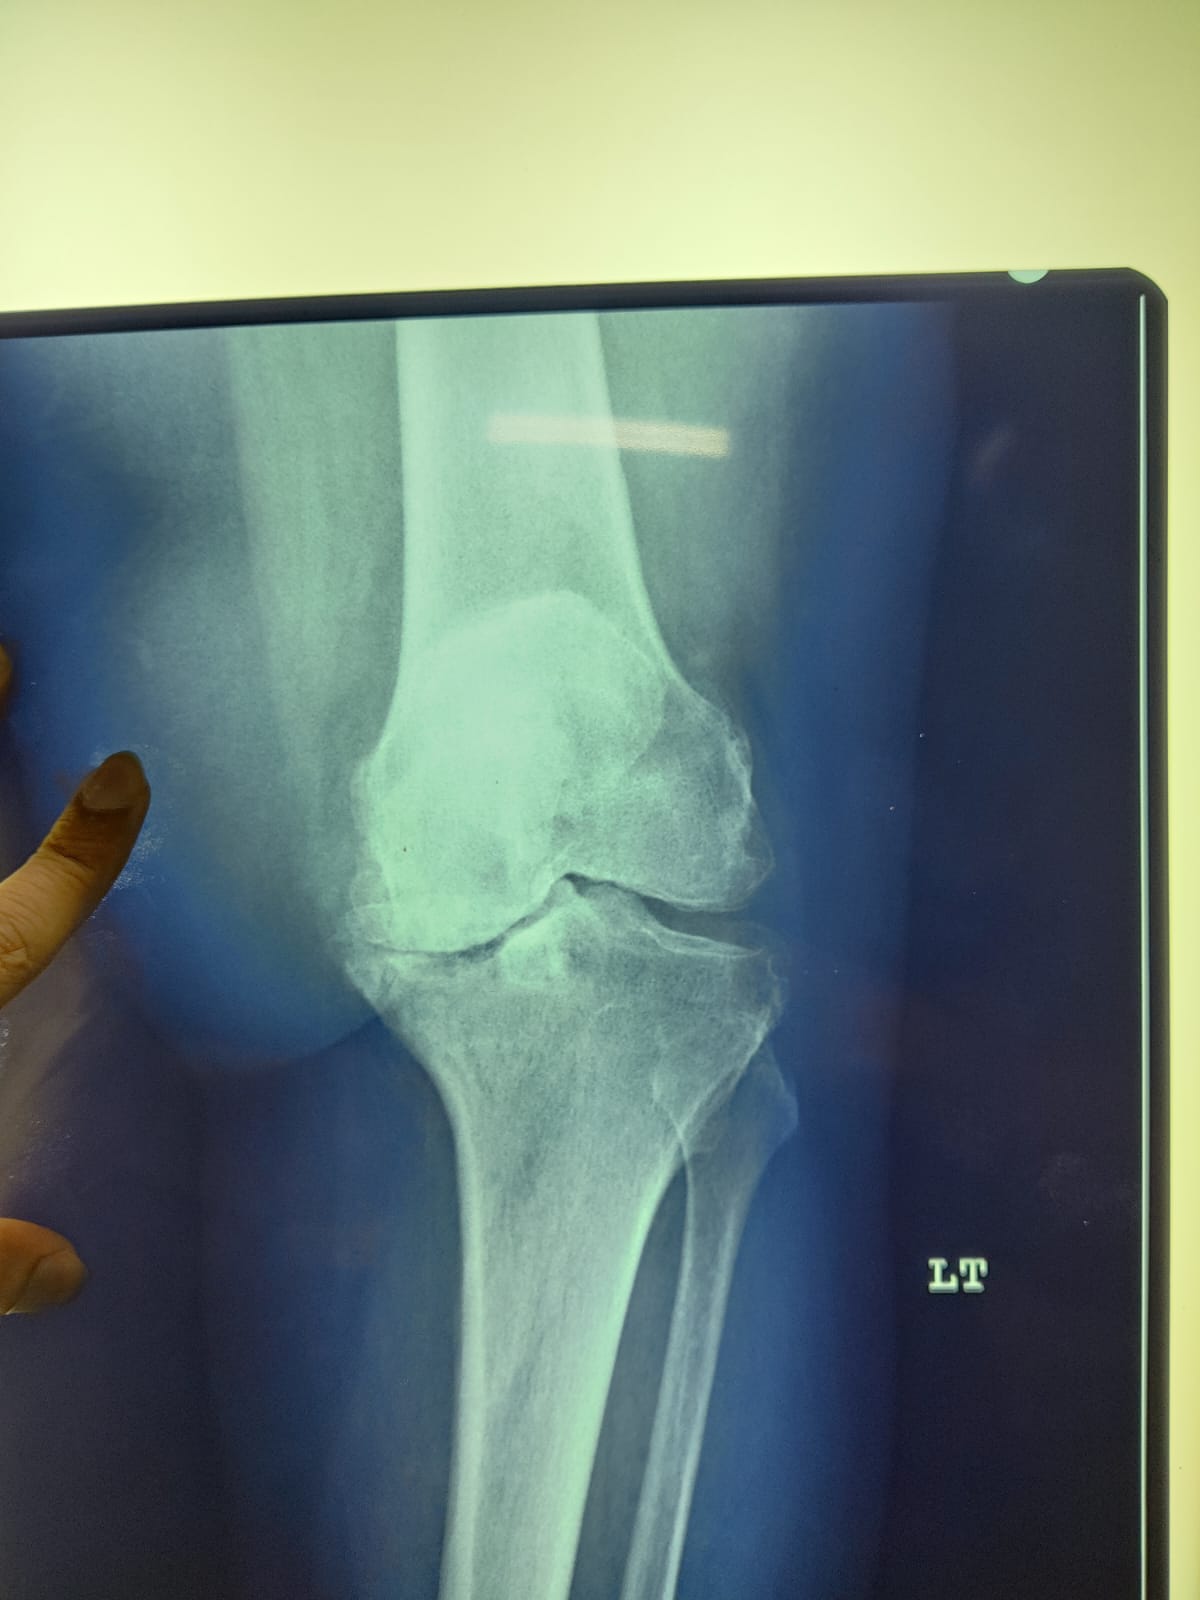

62 year old female with stage 4 OA

Pre-op images of Right Knee